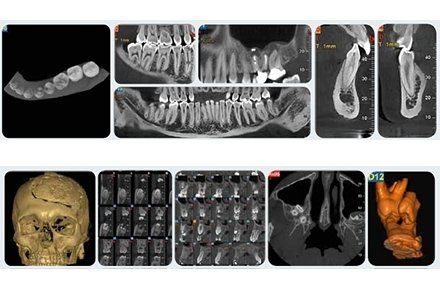

Radiografia specifica per la bocca

Lo studio si avvale di specifiche strumentazioni per assicurarti un’accurata analisi ortodontica. In primis, lo staff medico si affida all’alta tecnologia del sistema Cone Beam NewTon 5G XLUno, fondamentale per settori medici quali implantologia, endodonzia, chirurgia orale e ortodonzia, in grado di creare immagini 3D capaci di mostrare patologie potenziali e anomalie strutturali con una precisione senza precedenti; dall’altra si sottolinea la presenza della tecnologia SafeBeam™, il sistema più sicuro sia per i pazienti che per lo staff medico. Grazie a questo strumento, gli esperti eliminano qualsiasi possibilità di esposizioni radioattive, mantenendo un contrasto dell’immagine nitido e definito, a prescindere dalle dimensioni anatomiche o dalla densità ossea osservata.